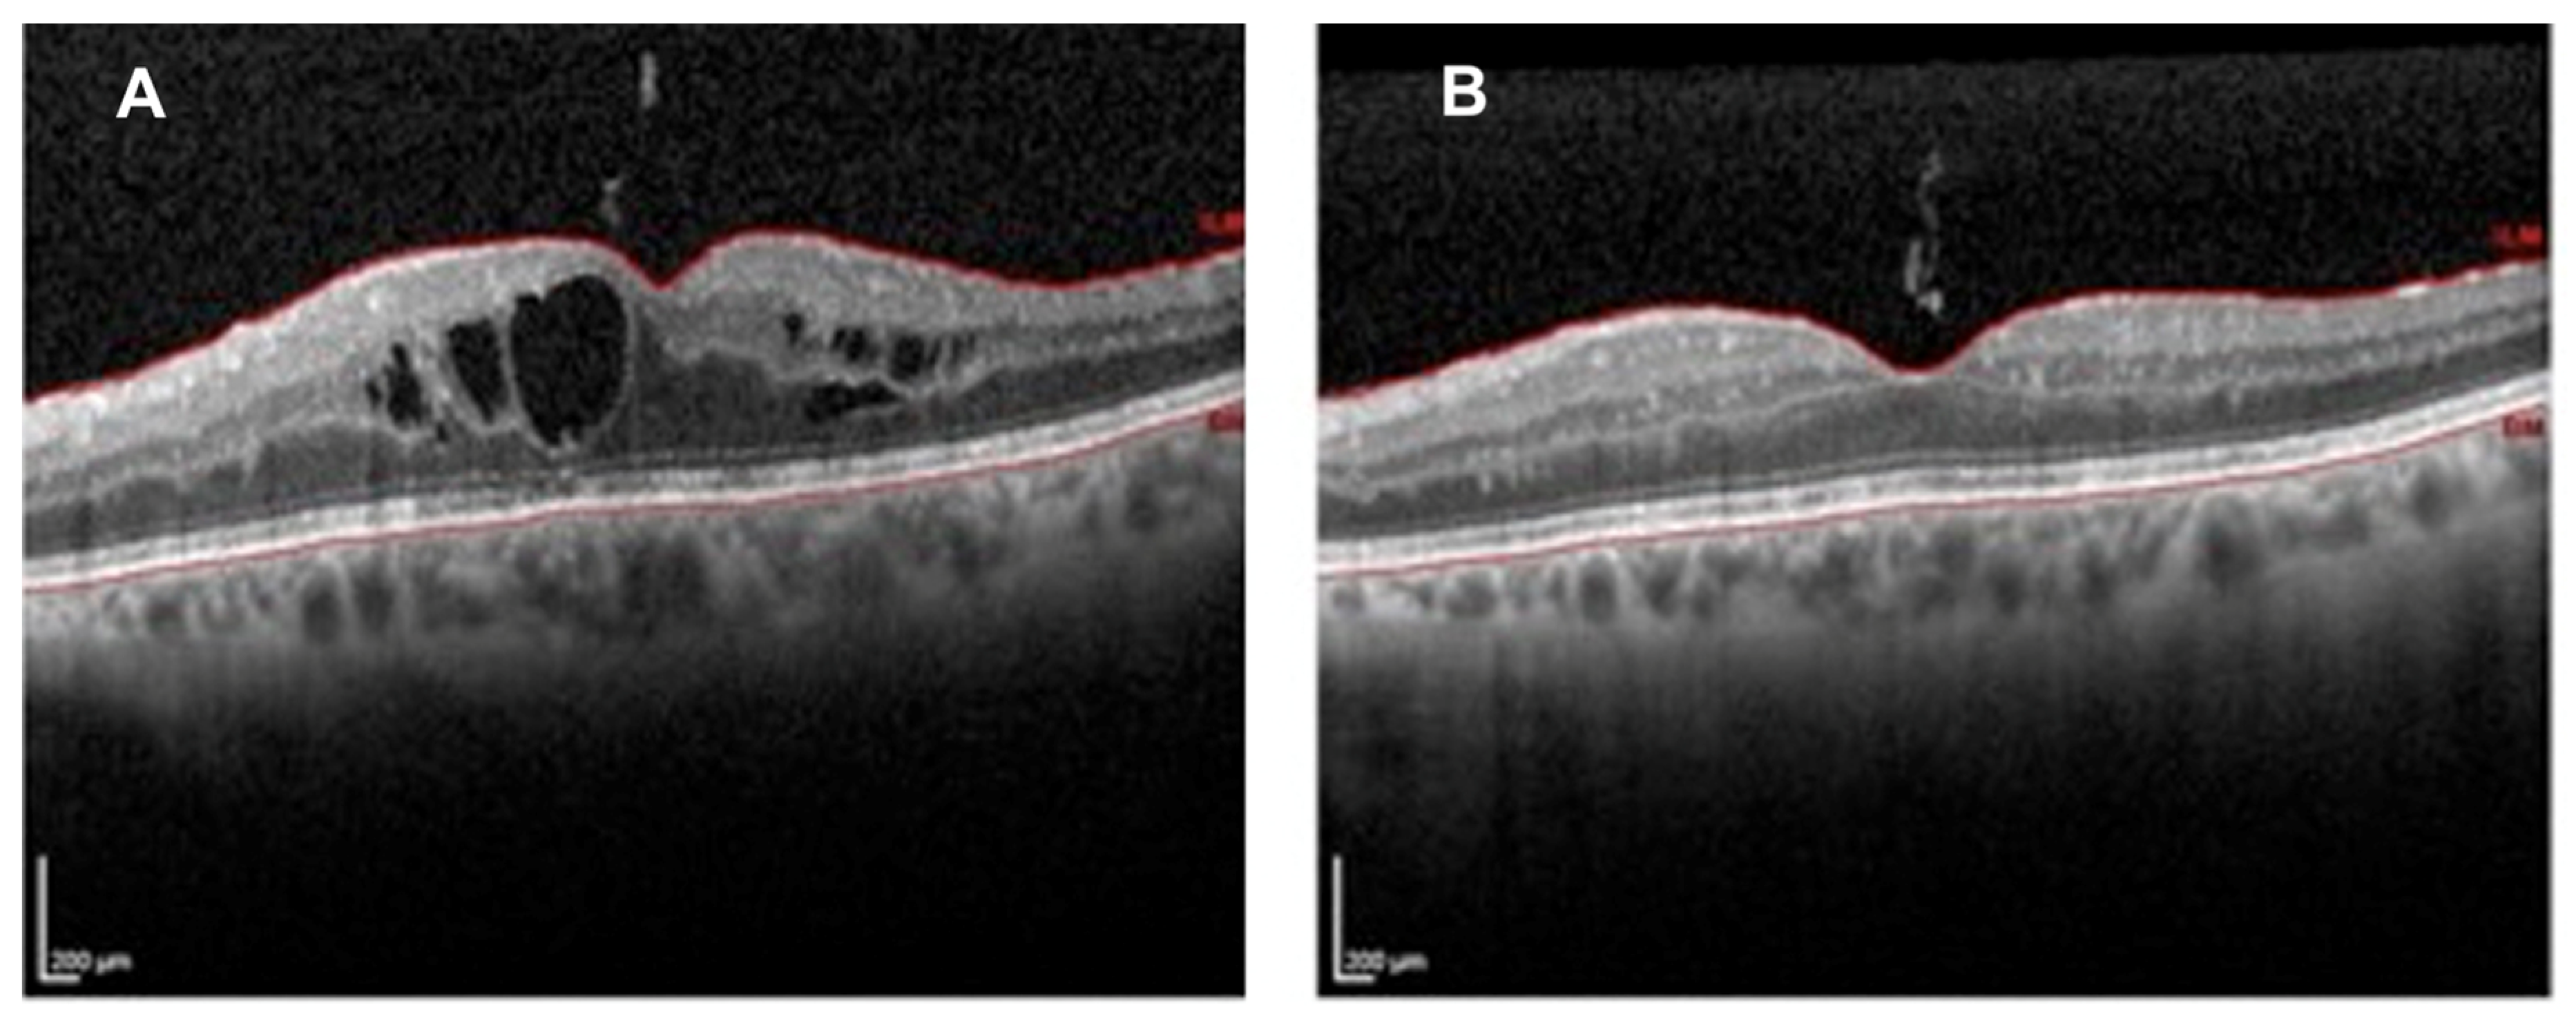

3.2. Radiation Maculopathy